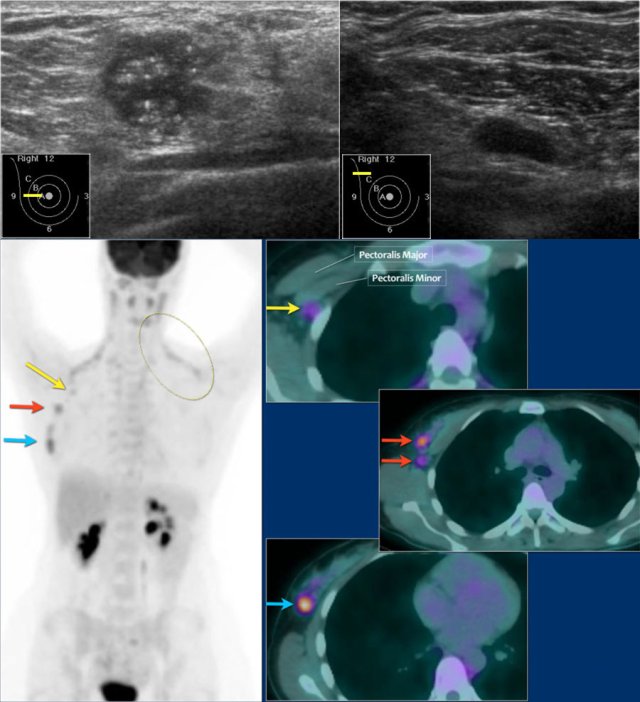

Here an example of a patient with advanced breast cancer.

The US of the breast showed an 18mm echopoor lesion with irregular margins and microcalcifications.

US of the axilla revealed a lymph node with no fatty hilum.

FNA was performed, and both the tumor and the lymph node were positive for adenocarcinoma.

The lesion was clinically staged as cT1N+. A PET-CT was performed.

On the upper PET-CT image a level II node is positive just underneath the pectoralis minor (yellow arrow).

Multiple axillary nodes were found but no systemic metastases.

Normal brown fat is seen along the neck and shoulder muscles on both sides (circle).

This patient was planned for neoadjuvant therapy and biopsies were taken for the determination of the tumor grade, hormone receptors and HER-2-neu-amplification.